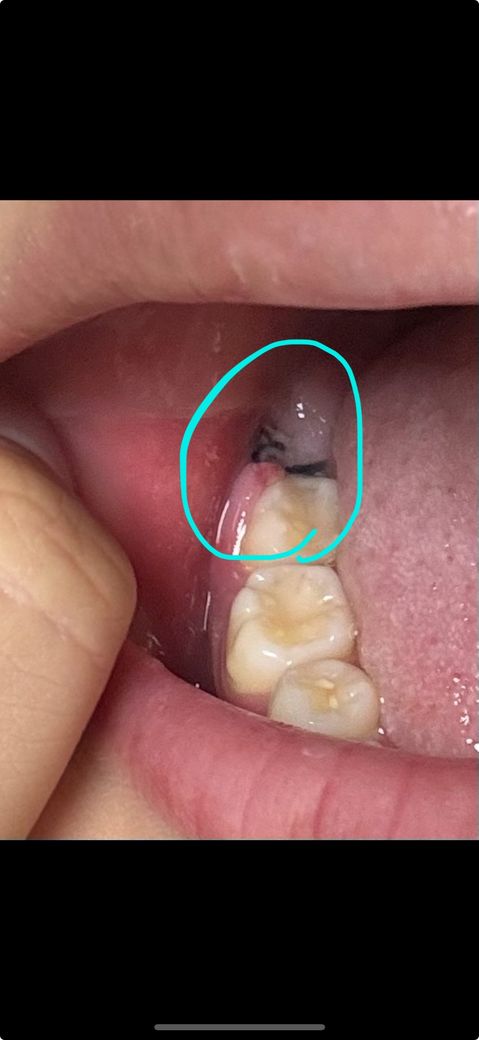

다만 사랑니와 맞닿아있던 어금니쪽(발치 부위 바로 앞) 잇몸이 사진처럼 굉장히 부어올라 있습니다.

이 부분의 붓기는 빠지기는커녕 자고 일어나면 더 붓는 것 같은데 정상인가요? 처방받은 약은 꾸준히 먹고 있습니다.

발치한 사랑니의 엑스레이 사진 함께 첨부하겠습니다.

• 1번 째 사진